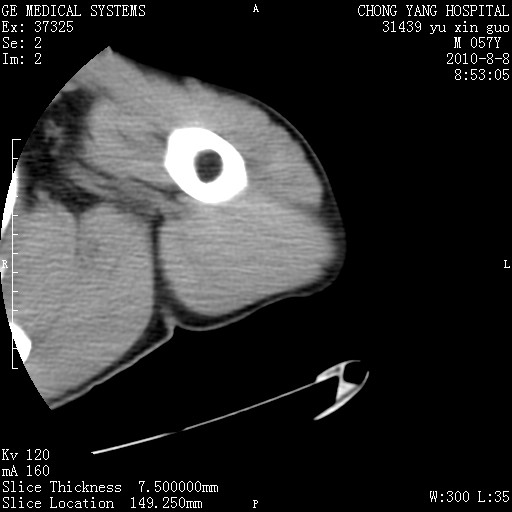

标题: CT28267:M57Y 上臂包块8年余。 [打印本页]

标题: CT28267:M57Y 上臂包块8年余。

典型脂肪瘤改变

包膜光滑、完整的脂肪密度肿块,支持脂肪瘤。